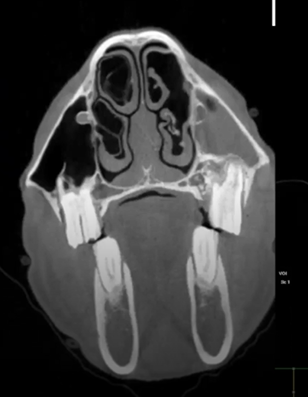

Read MoreThis 14 yo Percheron had plenty of dental issues. CT images show several missing teeth, expanded mandibles, a previous mandibular fracture, a severe shear mouth, and fluid in the sinuses.

Featured: JR Lund, University of Wisconsin-Madison